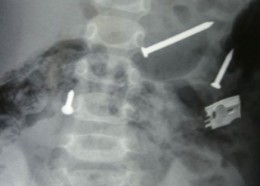

Чудни ренгенски снимки